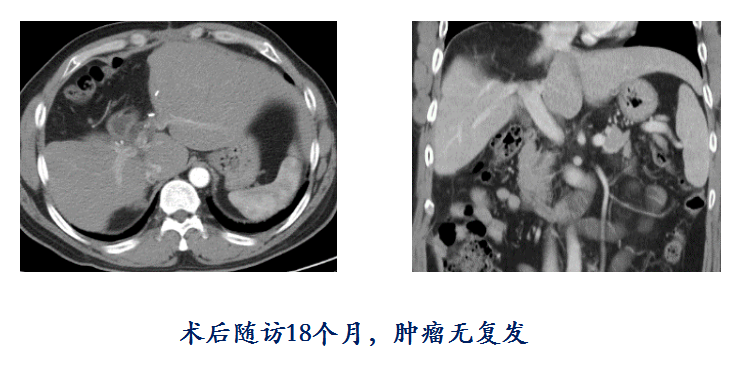

栓塞后再次造影显示,齐先生巨块型肿瘤的所有血管已完全阻断,术后1个月CT显示肿瘤坏死达到92.6%,肿瘤体积也缩小25%左右,肿瘤负荷显著降低。肝胆外科执行主任卢倩医生带领团队接力,为患者根治性切除肝中叶肿瘤,术后恢复良好,各项指标正常,至今无瘤生存18个月。齐先生第一次复查时激动地表示:“我是家里的顶梁柱,曾经一度觉得一切都完了,根本无法面对家里的妻子和四个孩子,这次手术不仅是救了我的命,更是救了我的家。”